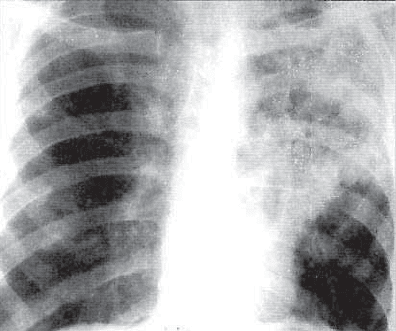

ТУБЕРКУЛЕМА ЛЕГКИХ

Туберкулема легких — клиническая форма туберкулеза, при

которой в легочной ткани формируется инкапсулированное

казеозно*некротическое объемное образование диаметром бо-

лее 12 мм.

Обнаруживают туберкулемы с одинаковой частотой как в

левом, так и в правом легком. Локализуются они чаще в на-

ружных отделах и субплеврально. Выделяют мелкие (до 2 см в

диаметре), средние (2—4 см) и крупные (более 4 см в диамет-

ре) туберкулемы, которые могут быть единичными или мно-

жественными.